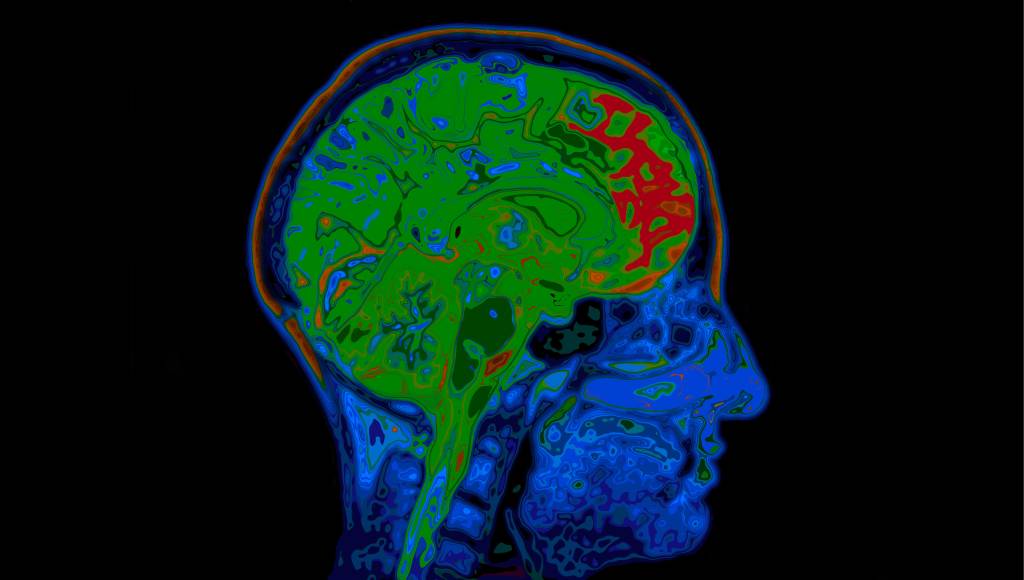

Bug em software de ressonância magnética pode invalidar 15 anos de pesquisas sobre o cérebro

Por Denis Russo Burgierman 6 jul 2016, 20h00 | Atualizado em 11 mar 2024, 11h11